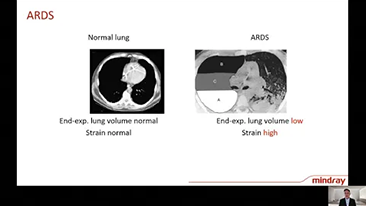

Solunum yolu hastal??? olan hastalar?n tedavisi i?in do?ru ventilat?r ayarlar?n?n se?ilmesi, olduk?a ?nemli bir konudur. Ventilasyon ekipman?n?n parametrelerini belirleme g?revi b├╝t├╝n├╝yle bir hekim taraf?ndan yap?ld???ndan, hekimin bu ayarlar?n se?imindeki bilgisi ve deneyimi, verece?i kararlar?n do?rulu?u ├╝zerinde do?rudan etkilidir. Hastalar?n destekleyici bak?m? paradigmas?, son 20 y?lda ?nemli ?l?├╝de de?i?ti. G├╝n├╝m├╝zde, bak?c?lar?n klinik kararlarda verimlili?i art?rmas?na ve hatalar? ortadan kald?rmas?na yard?mc? olmak i?in, klinik gereksinimler etraf?nda ?e?itli ventilasyon modlar? ve karar destekleme ara?lar? geli?tirildi.

Y├╝ksek ak??l? oksijen tedavisi, invaziv olmayan ventilasyon ve invaziv ventilasyonu entegre eden 3'├╝ 1 arada SV Serisi ventilat?rler, istikrarl? performans ve ?ok y?nl├╝ fonksiyonlar ile kullan?m kolayl???n? bir araya getirir. Ola?an├╝st├╝ akci?er koruyucu ?zellikleri ve bir?ok karar destek arac?, ?apraz enfeksiyon riskini azaltmak ve bak?c?lar?n g├╝nl├╝k rutinini kolayla?t?rmak i?in tasarland?.